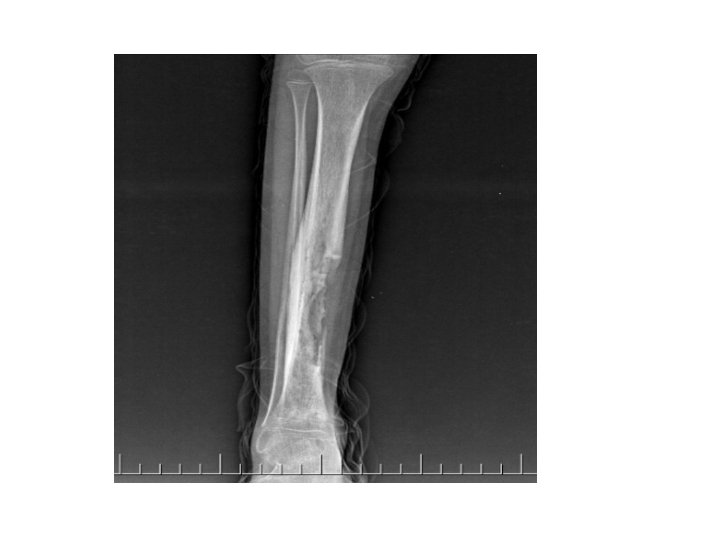

Chronic Osteomyelitis • • • Involucrum Sequestrum Cortical destruction Periosteal elevation Cloaca Pathological fracture

Chronic Osteomyelitis • Common causes : Staphylococcus aureus, Escherichia coli, Pseudomonas spp, Klebsiella spp, Salmonella spp. • Treatment : antibiotics(clindamycin, flouroquinolones, augmentin), sequestrectomy, saucerization, decortication.